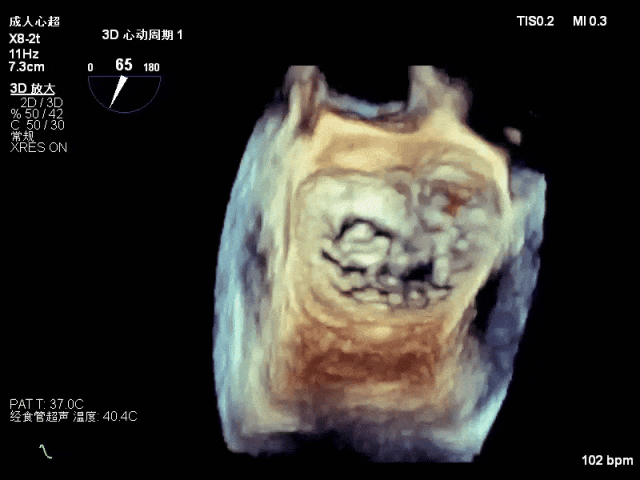

术前心超

退行性二尖瓣反流(DMR),P1/P2交界脱垂连枷(脱垂范围7mm,连枷间距4mm)

新分型:AAA型,MR 4+,VC:4×7mm

A1.5:20mm,P1.5:10mm,AP:30mm,MVA约3.8cm²

术中超声要点